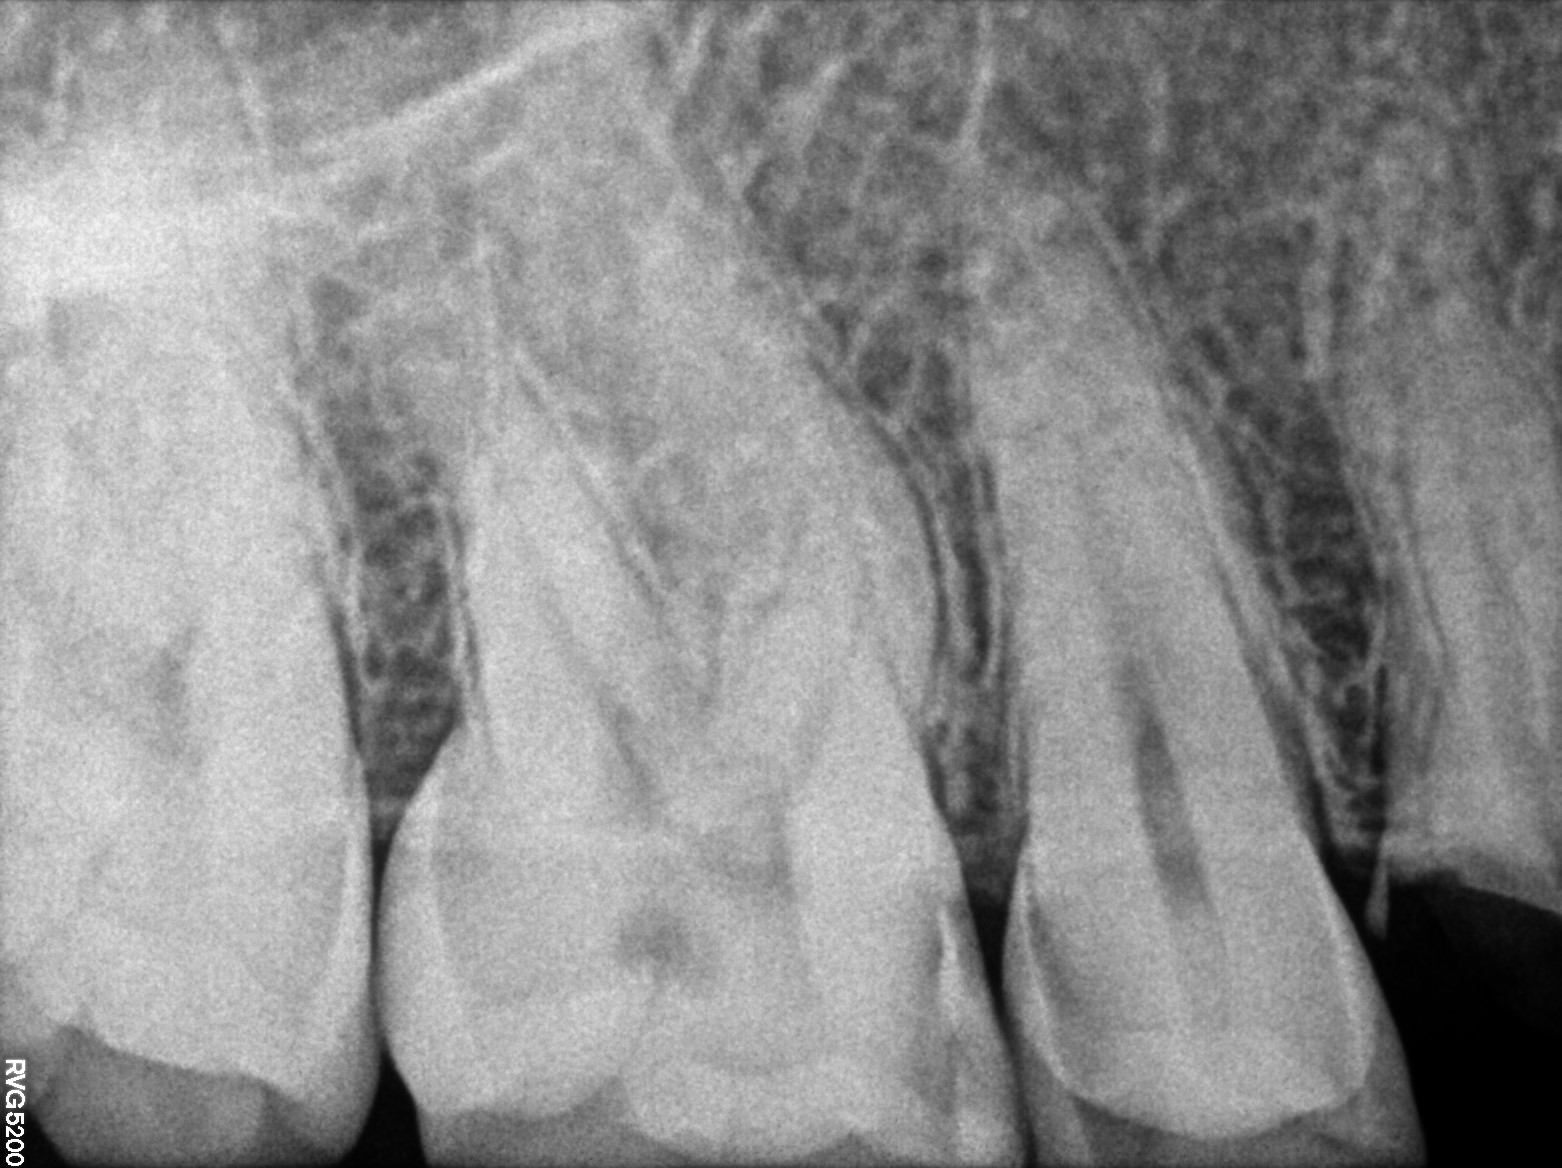

Dental Radiographs FHIR: DocumentReference · LOINC 24641-7

FHIR Bundle

xray_1772642539_0.jpg

24641-7

xray_1772642477_1.jpg

R55.jpg

xray_1770998647_1.jpg

R57.jpg

xray_1770476620_0.jpg

xray_1770998647_0.jpg

xray_1771259343_0.jpg

R56.jpg

xray_1772120353_0.jpg

R62.jpg

xray_1772642477_0.jpg